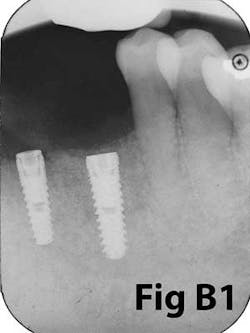

Fig. 7: Failing implants for mandibular overdenture were placed in atrophic mandible with inadequate attached tissue.Comparison